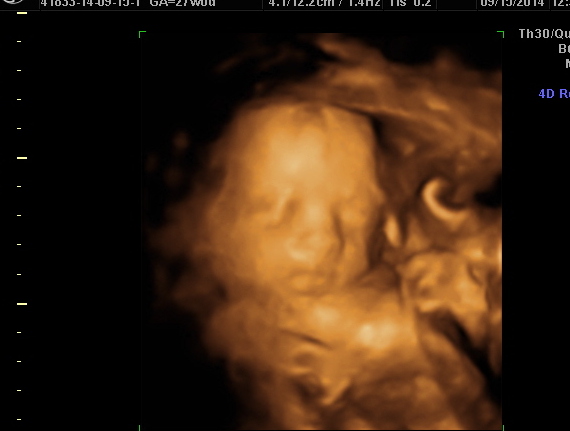

Cervix is "very long and closed" and there's plenty of fluid. Thank goodness! Then the u/s tech showed us our boy! I kept saying it was okay, as long as I knew he was okay, I didn't expect pictures. I didn't want anyone to think I was trying to milk a free ultrasound by faking BH concerns (I have a hard time with stuff like that). She was so sweet and said I was a worried Mama so she was going to give me a little reward!

So here's my son going, "Doh, Mom, don't worry so much!"